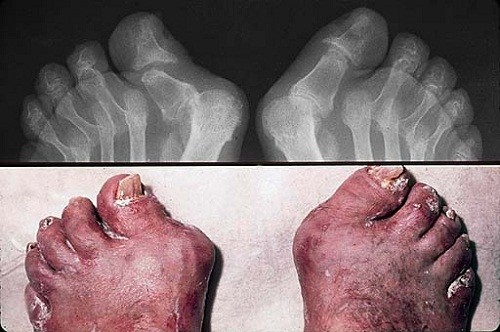

Vảy nến ở khớp chân

Đây là một trong những trường hợp vảy nến gây ra các vấn đề vô cùng nghiêm trọng cho người bệnh. Bởi lẽ, nó không chỉ ảnh hưởng về mặt thẩm mỹ mà còn ảnh hưởng trực tiếp đến cuộc sống của người bệnh.

Căn bệnh này có thể xuất hiện ở các khớp chân như khớp gối, khớp ngón chân, mắt cá chân. Khi mắc bệnh, các khớp sẽ sưng tấy, đỏ và khiến cho người bệnh khó khăn trong việc di chuyển, thường xuyên phải chịu những cơn đau từ khớp chân. Vảy nến ở khớp chân còn được gọi là viêm khớp vảy nến.

Khi có dấu hiệu của bệnh vảy nến khớp chân, cần phải đến ngay các trung tâm hay cơ sở y tế uy tín để được khám chữa bệnh. Nếu như không điều trị kịp thời và dứt điểm, vảy nến sẽ gây ra những ảnh hưởng vô cùng xấu cho người bệnh. Trường hợp xấu nhất, người bệnh có thể sẽ bị tàn tật.

Vảy nến khớp chân